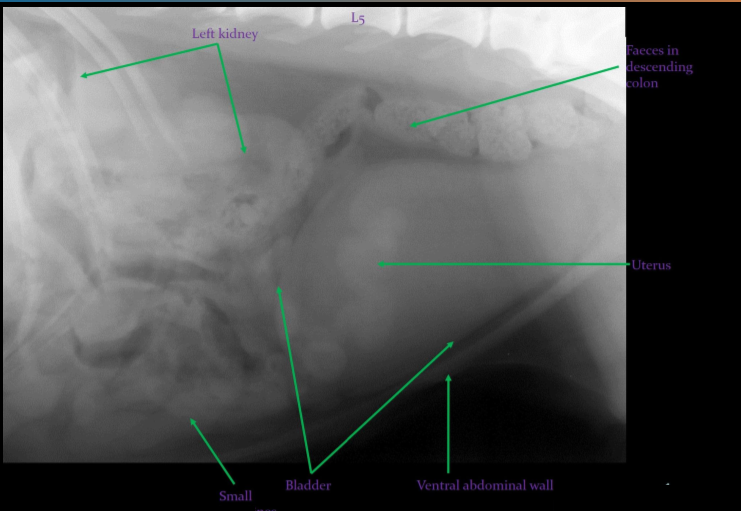

Label this radiograph of a bitch

Label this radiograph of a bitch in metoestrus

What is abdnormal?

Uterus contains fluid = pyometra